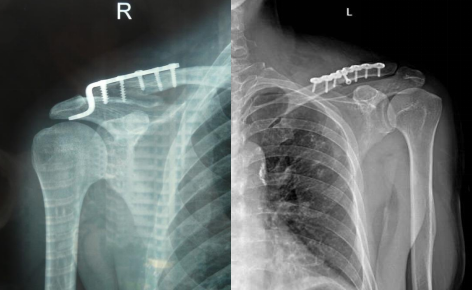

锁骨骨折